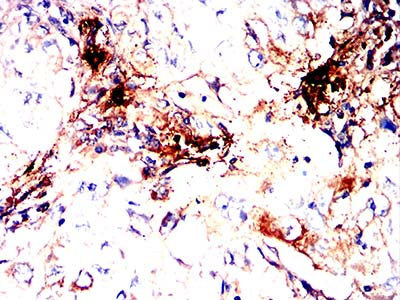

分类: 科研抗体货号: 32406别名: TPS1; TPS2; TPSB1; TPSB2; Tryptase-2应用: IHC,IF,FCM反应种属: Human